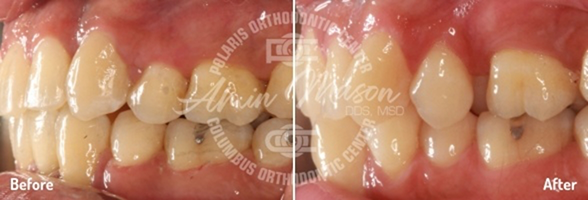

Case 5

This 17-year-old patient came into our office with a multitude of problems we’ve helped many other people fix: teeth crowding, an underbite, and a crossbite of the back teeth (where the upper and lower teeth are offset from left to right). Each of these issues was quite severe, however, and the patient was previously told he needed surgery to correct them all. He said he didn’t want to undergo surgery, so Dr. Mason put together a customized treatment plan. First, he placed a temporary anchorage device (TAD) supported expander to increase the size of the patient's hard palate, and he also used another TAD on the lower teeth to close the spaces. Then, Damon damon self-ligating braces helped move the teeth into their ideal positions. One of the patient’s lower premolars was removed as well. In the end, the patient was able to avoid surgery and achieve excellent results that he could not believe.